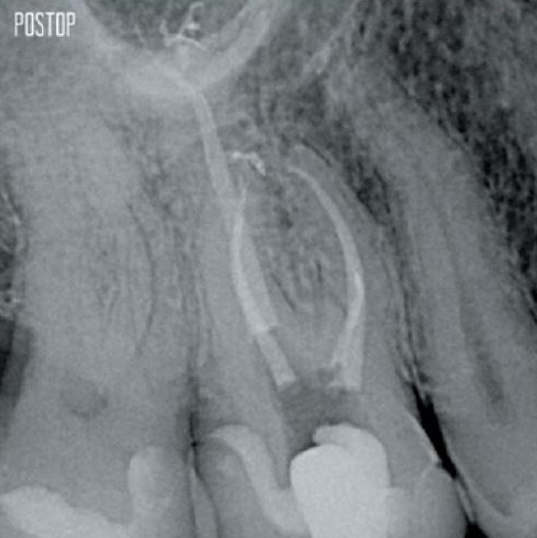

TruNatomy® preserves as much dentin as possible1 and offers a complete solution including matching irrigation and obturation.

The union of the file geometry, regressive tapers and the slim, highly-flexible wire enables efficient root canal treatment while removing only dentin where clinically needed.1

More dentin preserved. Appropiate shaping, irrigation, and obturation ensured.

Photos courtesy of Dr. Ahmed Salman

Yes, the TruNatomy Conform Fit® gutta-percha points are designed to perfectly match the preparations made with TruNatomy files and ensure an optimal obturation.